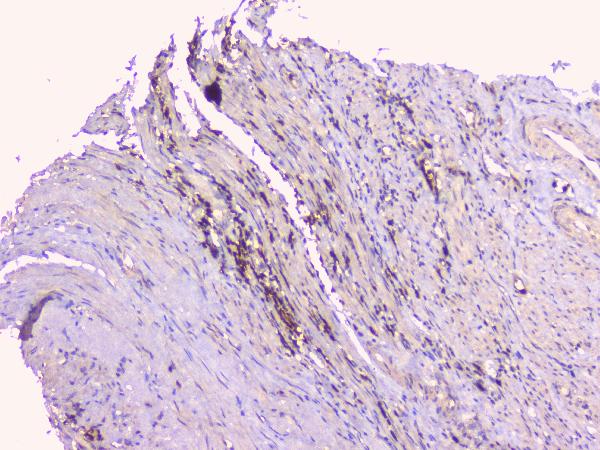

IHC analysis of OPG/TNFRSF11B using anti-OPG/TNFRSF11B antibody (A00863).

OPG/TNFRSF11B was detected in a paraffin-embedded section of human appendicitis tissue. Biotinylated goat anti-rabbit IgG was used as secondary antibody. The tissue section was incubated with rabbit anti-OPG/TNFRSF11B Antibody (A00863) at a dilution of 1:200 and developed using Strepavidin-Biotin-Complex (SABC) (Catalog # SA1022) with DAB (Catalog # AR1027) as the chromogen.